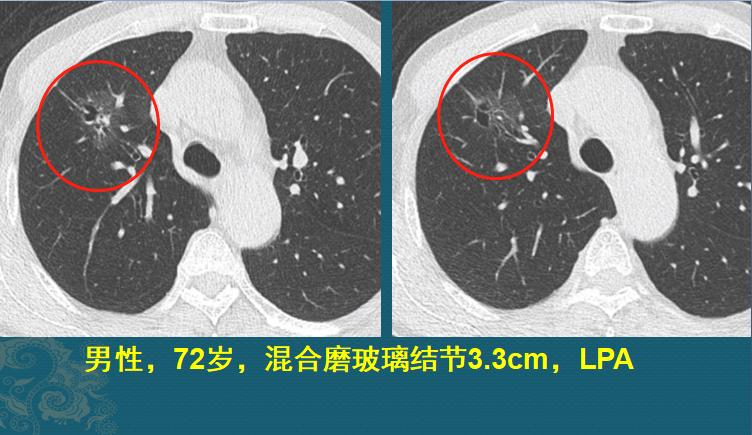

第一种,贴壁生长为主的肺腺癌,治疗效果很好

这位老爷子72岁,体检发现右上肺混合磨玻璃结节,看着挺大,3.3cm,但实性成分很少,以磨玻璃为主(磨玻璃反映的是贴壁生长为主的高分化成分),手术病理是浸润性肺腺癌,贴壁型生长为主,没有低分化成分,清扫数枚淋巴结均无转移,这种的治疗效果很好,不需要后续治疗,定期复查即可。

简单来说,如果手术后医生让你定期回来复查,那就开开心心回家康复就好,说明分期很早,治愈几率很高,不要胡思乱想啦。